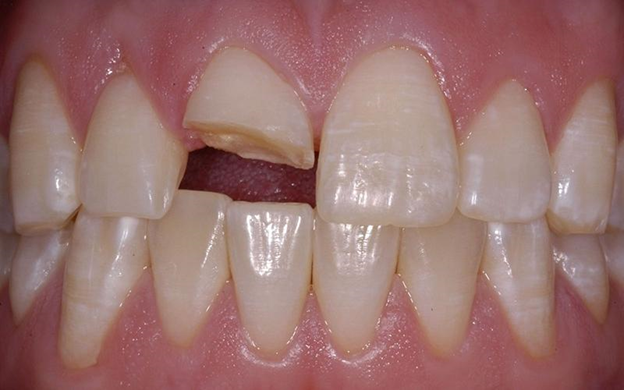

- ✨ Chấn thương răng hoặc răng bị vỡ

- Răng bị gãy, nứt hoặc chịu tác động ngoại lực sẽ làm tủy răng lộ ra ngoài. Đây là điều kiện lý tưởng để vi khuẩn tấn công trực tiếp, gây viêm tủy cấp tính nếu không được điều trị kịp thời, đồng thời làm tăng nguy cơ mất răng vĩnh viễn.